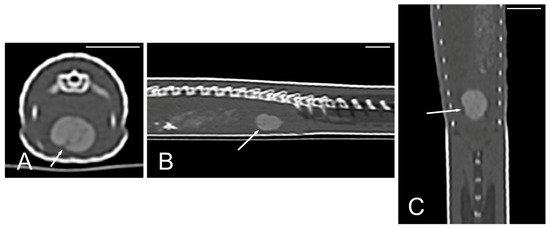

The kidneys and ovaries were identified only in postcontrast CT images. The kidneys appeared as a pair of soft tissue attenuating elongated structures in a ventrolateral position to the spine, in the caudal third of the coelomic cavity. They were best seen in the transverse and dorsal planes. Their margins were not well defined. The aorta was only seen in the midline between them (Figure 13). We could distinguish ovarian follicles only in one individual and they appeared as hypoattenuating rounded to oval structures, bounded by fine slightly hyperattenuating margins (Figure 14). The ureters, urinary bladder, oviducts, testes, and hemipenes were not recognizable in our CT studies.

Figure 13.

The postcontrast CT images of Pseudopus apodus in the dorsal (A) and transverse (B) planes showing both kidneys (white arrows) and the aorta (black arrow) between them in the dorsal part of the coelomic cavity, just ventral to the spine. Bar = 10 mm.

The cloaca was identified in the caudoventral part of the coelom in only two animals due to the presence of hyperattenuating content in the lumen (urate salts) (Figure 15).

Figure 15.

The CT images of Pseudopus apodus in the transverse (A), sagittal (B), and dorsal (C) planes showing hyperattenuating content (urate salts) (arrows) in the cloaca. Bar = 10 mm.